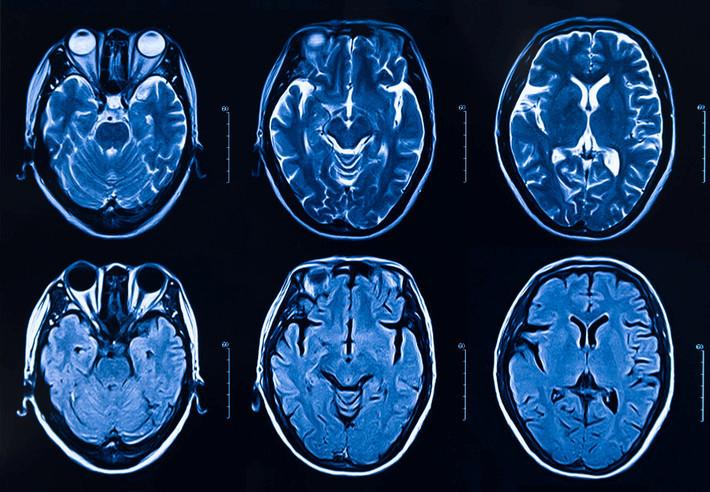

Çoğu zaman diş tedavileri sırasında ortaya çıkan uyuşukluk ve hafif rahatsızlıklar normal karşılanır. Ancak, bir hastanın bu semptomlar uzayıp yaygınlaştığında, altta yatan ciddi bir sorunun işareti olabileceği önem kazanır. McInerny’nin yaşadığı durum, tedavi sonrası ortaya çıkan nadir bir nörolojik rahatsızlık olan hemifasiyal spazm ile ilgiliydi.

İlk başta endişelenmeden diş hekimine gitti, ancak zamanla belirtiler şiddetlenip günlük yaşamını etkiler hale geldi. Sağ yüzünün bir tarafında hissedilen ani kas seğirmeleri, göz kapağında istemsiz kapanma ve yüzün diğer bölümlerinde oluşan garip hisler önemli bir uyarı niteliğindeydi.